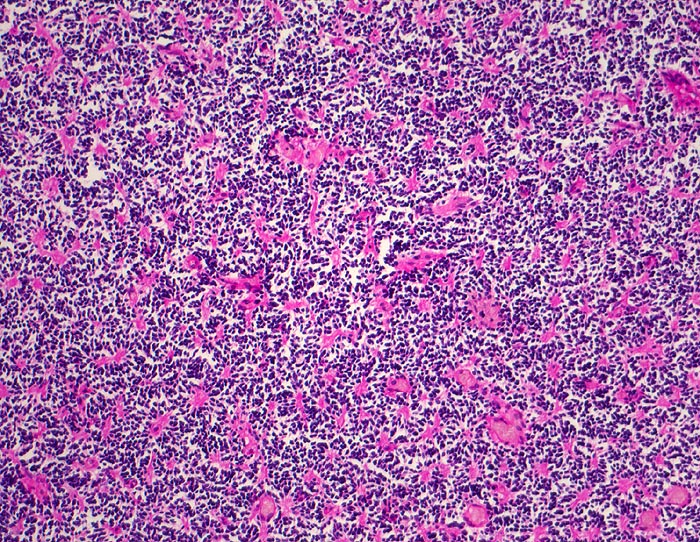

Medulloblastom: Homer Wright Rosetten

Monomorpher Zellrasen mit hyperchromatischen Zellen ohne erkennbares Zytoplasma. Multiple Homer Wright Rosetten erkennbar am eosinophilen Zentrum aus Zellfortsätzen.

Knabe mit Kopfschmerzen und morgendlichem Erbrechen ohne Übelkeit

Histologie

Vergrösserung

100

Alter

7

männlich